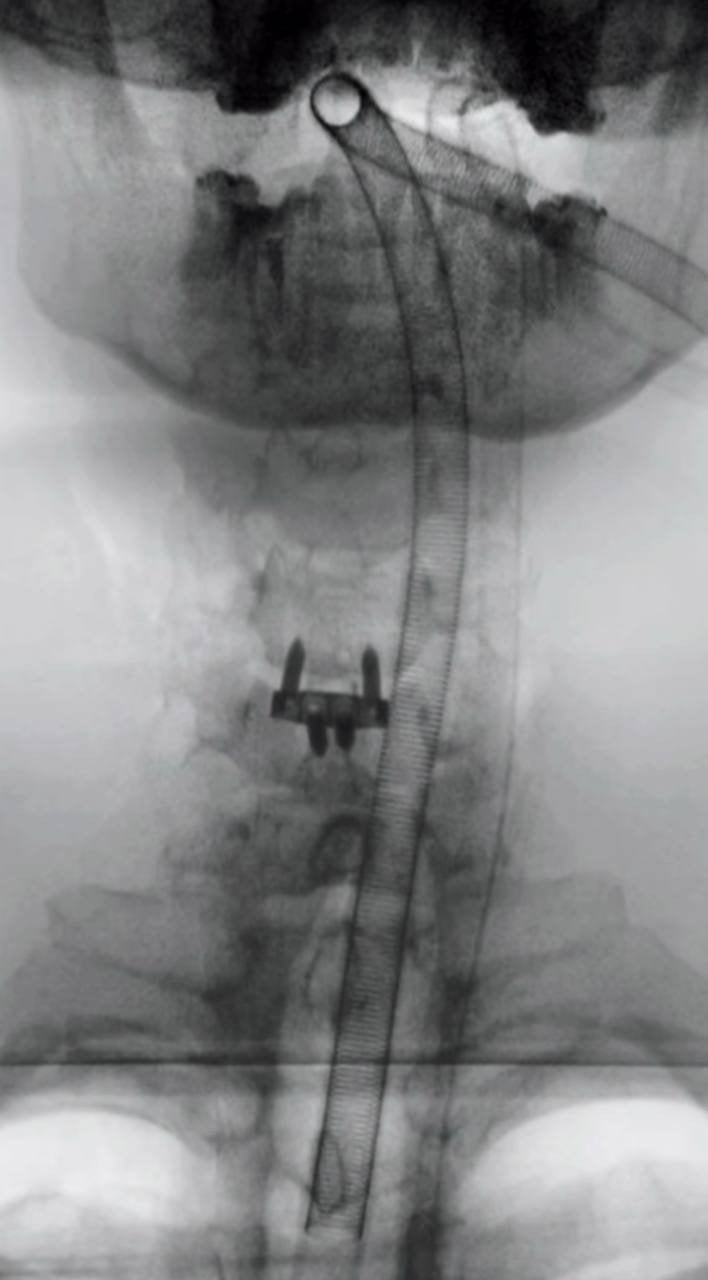

Як з’ясувалося, проблеми почалися ще три роки тому після невдалого сальто. Через травму у нього утворилася грижа в шиї, яка спричиняла постійний біль і навіть періодичне оніміння руки. Медики в Україні та за кордоном довгий час відмовляли його від операції через високий ризик ураження спинного мозку.

Хірургічне втручання минуло успішно — блогеру встановили спеціальний імплант у шию. Після наркозу Ніколас Карма уже вийшов на зв’язок із підписниками та показав перші кадри з операційної та одразу після під час відновлення. На шиї у нього помітний медичний пластир, однак сам блогер почувається значно краще.